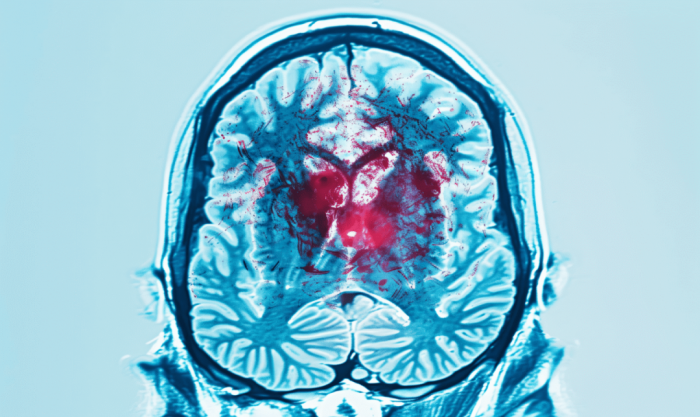

10月29日是世界卒中日。 时下,计算机断层扫描(CT)和磁共振成像(MRI)已成为患者在体检或出现头晕、头痛时的常规检查。拿到影像报告,有些人看到“缺血灶”“腔梗灶”和“多发、散在梗死灶”等字样时,便如临大敌。事实上,“腔梗灶”“缺血灶”只是影像学上的表现,并不等同于脑梗死,它们被统称为无症状性脑血管病,是头颅影像学上最常见的表现。 影像学发现和疾病之间并不是简单的一一对应关系。就像在家里发现一片水渍,我们只能说这个地方有漏水的迹象,但并不能确定是水管坏了、屋顶漏水,还是其他原因造成的,也不好确定什么时间产生的这片水渍。 同样,影像检查中发现的病灶并不一定指向一种特定的疾病,它们可能与多个问题有关。因此,影像学结果只是帮助大家了解健康状况,真正的诊断还需要结合其他检查和医生的判断来综合考虑。 那么,大家该如何看待这种无症状脑血管病呢? 发现“缺血灶”是不是大脑缺血了 发现“缺血灶”并不是大脑真的缺血了,而是指在影像学检查(CT或MRI)中发现脑组织存在异常信号区域,通常是指血管源性脑白质高信号。它并不是一个医学诊断,也不是一个疾病名称,而是MRI对一种影像改变的描述。 老年人中,少量的脑白质高信号,并不影响大脑功能。医生认为这样的脑白质高信号的存在是属于正常的,就像人额头的皱纹和头上的白发,是衰老的表现。如果脑白质高信号累积或扩大,可能导致以下问题: 一是认知功能下降,影响执行功能和记忆。严重时还可能出现步态障碍、吞咽困难和排尿功能异常等症状。二是卒中风险增加。脑白质高信号可能是脑梗死的前兆,尤其是当其合并其他血管危险因素(如高血压、糖尿病)时。 “缺血灶”会转化为脑梗死吗 这是大家最担心的问题。少量“缺血灶”在绝大多数的情况下与未来的脑梗死风险增加没有绝对的关系;但当“缺血灶”过多或持续加重,不好好控制高血压、糖尿病、高血脂等危险因素时,脑梗死就会发生,即平常所说的中风或脑梗死,可表现为嘴歪眼斜、肢体无力等症状。 为了预防“缺血灶”进一步增多或恶化,建议大家做到以下几点。 调整生活方式 ★戒烟限酒。 ★保持低盐、低脂、高纤维饮食。 ★维持健康体重,体质量指数(BMI)保持在18.5~23.9。 ★规律作息,避免熬夜和过度疲劳。 ★保持良好的心情。 ★坚持定期运动,建议结合自身体能,以户外运动及有氧运动为主,保持中等强度的有氧运动每周至少150分钟。 ★监测血压、血糖和血脂,如有这些血管危险因素,要遵医嘱服药。 遵医嘱检查 定期(半年至一年)进行体检,包括血压、血糖、血脂、同型半胱氨酸等检查。如果发现“缺血灶”,不用过度惊慌,建议到医院就诊,由专业医师评估并制定进一步的检查及治疗方案。 有“腔梗灶”是得了脑梗死吗 “腔梗灶”也只是影像学发现,这不代表现在就得了脑梗死,只是说明大脑里有个陈旧性的病灶,其确切病因并不清楚,可能是之前得过脑梗死,也可能是与年龄相关的扩大的血管周围间隙,需要医生进行评估。因为症状可能较轻,甚至没有症状,尤其是病灶位于非功能区或非要害部位,所以患者体检前并没有注意到。 不过,报告上的“腔梗灶”是值得关注的。因为这提示大脑发生过一些病变,可能脑血管已经有问题,与高血压、高血脂、糖尿病等慢性病控制不良有关。如果放任不管,反复多发性腔隙性脑梗死累积,患者就会出现步态障碍、精神障碍、认知障碍、尿便失禁等症状。 为了预防“腔梗灶”进一步增多或发生急性卒中,我们需要积极改善生活方式,控制血管危险因素,定期前往医院进行随访。 查出问题是否需要服用药物 关于影像报告中的“缺血灶”和“腔梗灶”,很多人最关心的就是是否需要服用阿司匹林和他汀类药物。 依据《中国无症状脑梗死诊治共识》及《中国脑血管病一级预防指南2019》,不建议单一的腔隙性梗死不伴有任何血管危险因素(如高血压、糖尿病等)的患者使用阿司匹林等抗血小板药物和他汀类药物; 建议有血管高危因素的患者到医院就诊,经过医生的评估,决定是否需要口服药物; 出现认知能力显著下降、肢体活动不灵、说话含糊不清等症状的腔梗死患者也需要经医生确诊病因,评估是否需要药物治疗。 建议40岁以上男性和绝经后女性每年进行血脂检查,血脂升高的患者应在医生的指导下进行规范治疗。 提示: 如果出现突发的口角歪斜、手脚无力、吐字不清等症状,这可能就是真正的卒中了,应尽快到就近的卒中中心就诊或及时拨打“120”急救电话。/健康科普